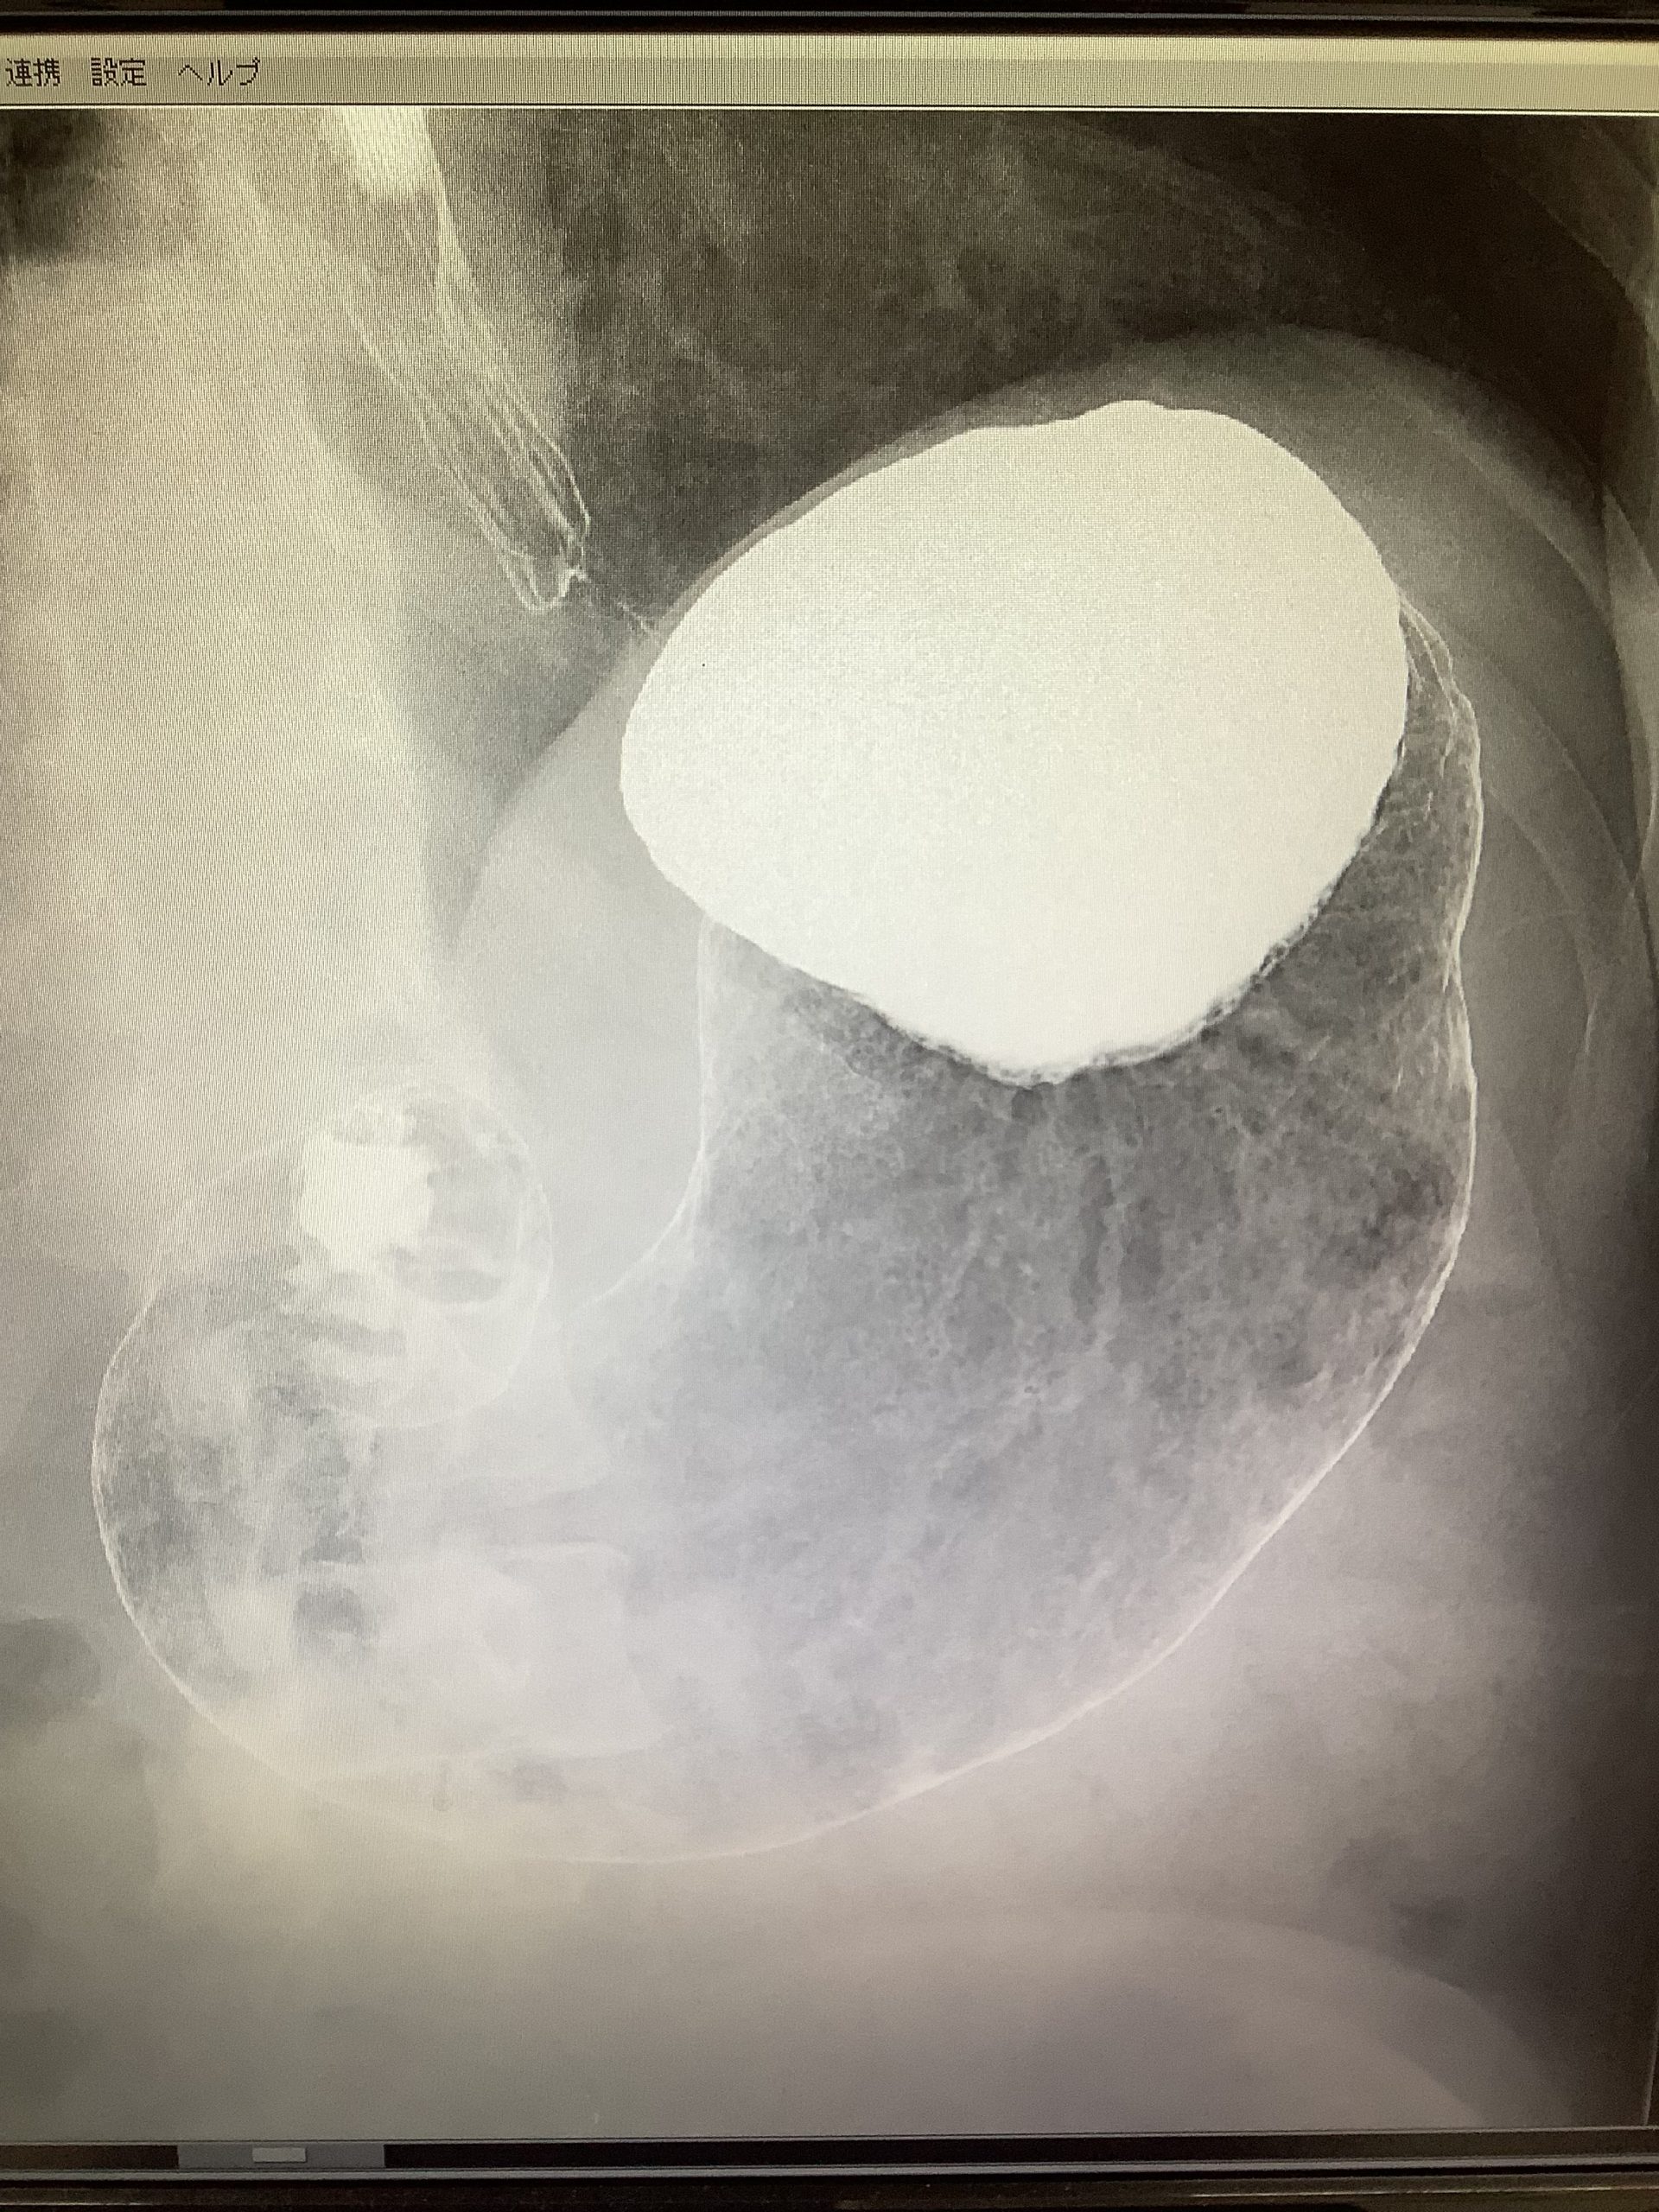

検診前の絶飲食のなぜ❓

検診の時、絶飲食となっていますがなぜでしょうか

血液検査や胃の検査をする際、精度や正確な情報に影響を与えてしまうからです。

バリウムの検査や胃カメラなどは、胃に内容物が無いようにするため食べ物は前日の21時までになるべく済ませてください。